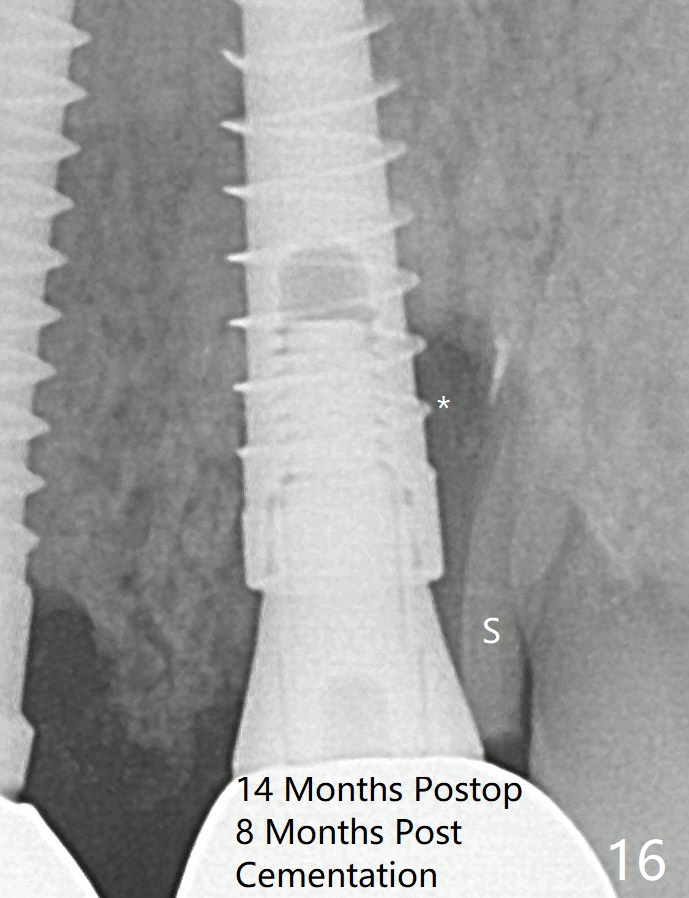

It appears that the socket shield (Fig.16 S) causes infection and loss of bone graft (*).